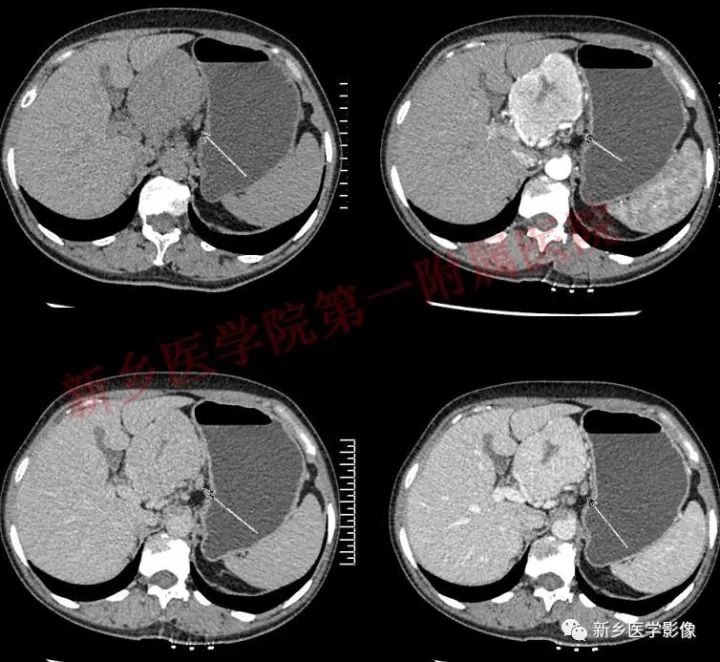

肝胃间胰腺前上方见类圆形肿块,边界较清,大小约8.2cm×4.6cm×5.9cm,密度欠均匀,内见点状钙化,增强呈不均匀明显强化,内见片状低密度灶无强化区,其下部与相邻胰腺分界不清,周围见粗大回流血管影回流至门静脉,病变左侧及腹膜后、胃壁小弯侧见数个卵圆形稍大淋巴结及结节影,部分呈环形强化。

可发生于全身各部位的淋巴结,沿全身淋巴结链分布,但最好发生于纵隔、肺门和腹膜后区域。约60-%~70%发生于胸部,约20%发生于腹部,以腹膜后最常见。

GLNH钙化较少,可见于5%~10%的病例,且仅见于局限型透明血管型。

GLNH另一个特征是瘤灶内极少伴有出血和坏死灶,尽管部分病例呈不均匀性强化,但瘤灶内的低密度影并非坏死灶。